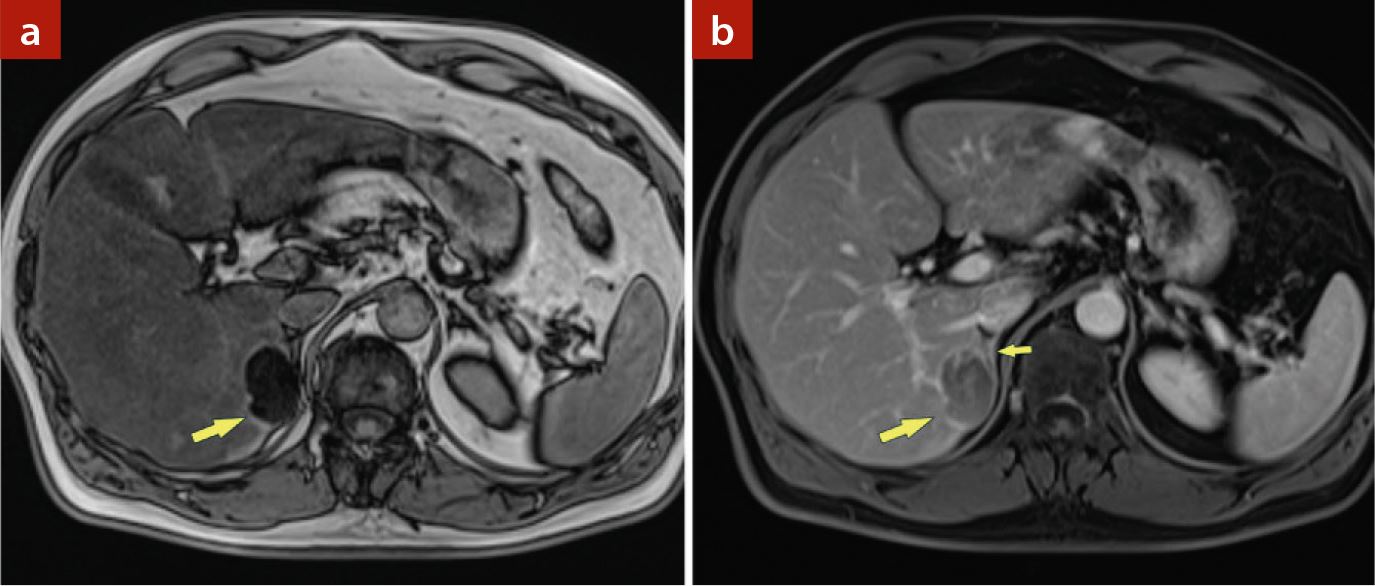

Bei einem 50-jährigen Patienten wurde auswärts in einer Sonografie eine unklare Raumforderung im rechten Leberlappen festgestellt. Der Patient wies keine Vorerkrankungen auf, keine chronische Lebererkrankung, die Leberfunktionsparameter waren im Normbereich. Es wurde daraufhin eine kontrastmittelverstärkte Multidetektor-Computertomografie (MDCT) durchgeführt, die eine ausgeprägte diffuse Steatose der Leber zeigte, mit einer 3,9 cm großen subkapsulären Raumforderung im rechten Leberlappen (S 6/7). Diese Läsion war eindeutig fett-haltig (Dichte nativ, –8 HU) und zeigte nach Kontrastmittel (KM) ein geringes Enhancement (▶Abb. 1). Zur weiteren Abklärung wurde der Patient an unsere Abteilung verwiesen, wo eine Magnetresonanztomografie (MRT) mit extrazellulärem gadoliniumhaltigem KM durchgeführt wurde. Auch in der MRT war eine ausgeprägte Verfettung des Tumors und eine KM-Aufnahme zu sehen (▶Abb. 2). Abgesehen von der diffusen Steatose der Leber fand sich kein Hinweis auf eine Lebererkrankung.

Die Multidetektor-Computertomografie (MDCT) zeigt a) in der Nativserie eine 3,9 cm große, fetthaltige Raumforderung im Lebersegment 7 subkapsulär (Pfeil) und eine diffuse Dichteminderung der Leber als Ausdruck einer Steatose. Die kontrastmittelverstärkte MDCT b) axial und c) coronal zeigt eine Kontrastmittelaufnahme des Tumors (Pfeil) und auch die Nähebeziehung zur rechten Nebenniere (kleiner Pfeil). Der Ursprungsort der Raumforderung ist aber eindeutig in der Leber.